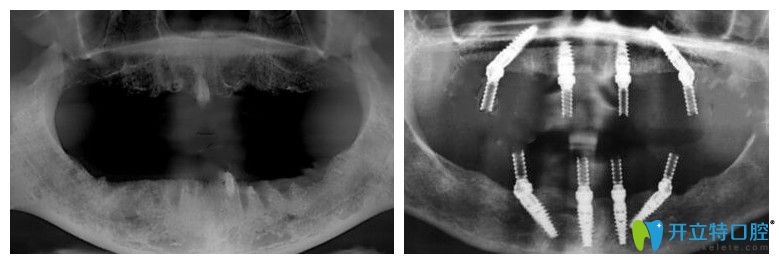

65岁,薛老师;种植前上颌牙齿全部脱落,下颌就剩下四颗残根;之前戴过活动假牙,但因为时间长了戴上很容易掉,所以才考虑做全口种植牙。下面是做种植牙前后的CT片:

薛老师说没做种植牙前听别人说价格特别贵,但是在靖江艾齿嘉口腔面诊、拍片检查后,陈涛医生建议自己做ALL-ON-4全口种植牙,上下颌各植入4颗种植体,就能支撑全口牙冠,这种方法不仅让自己省了很多钱,而且吃东西的咀嚼力也强。